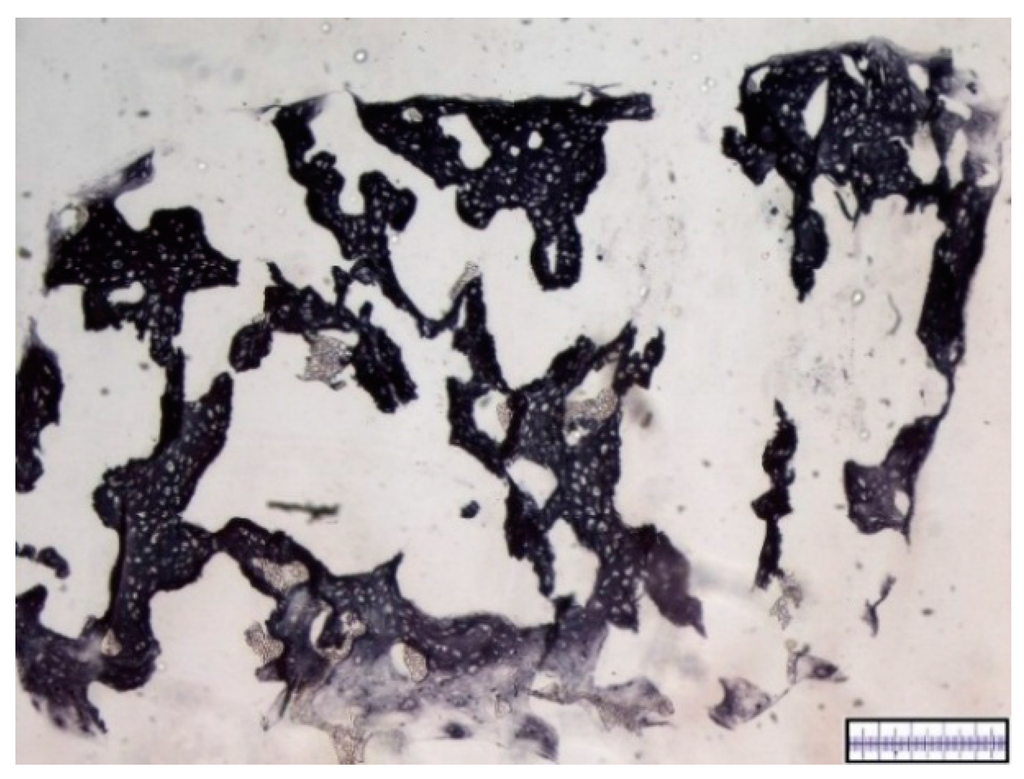

3.2. Interconnectivity of Scaffold Pores